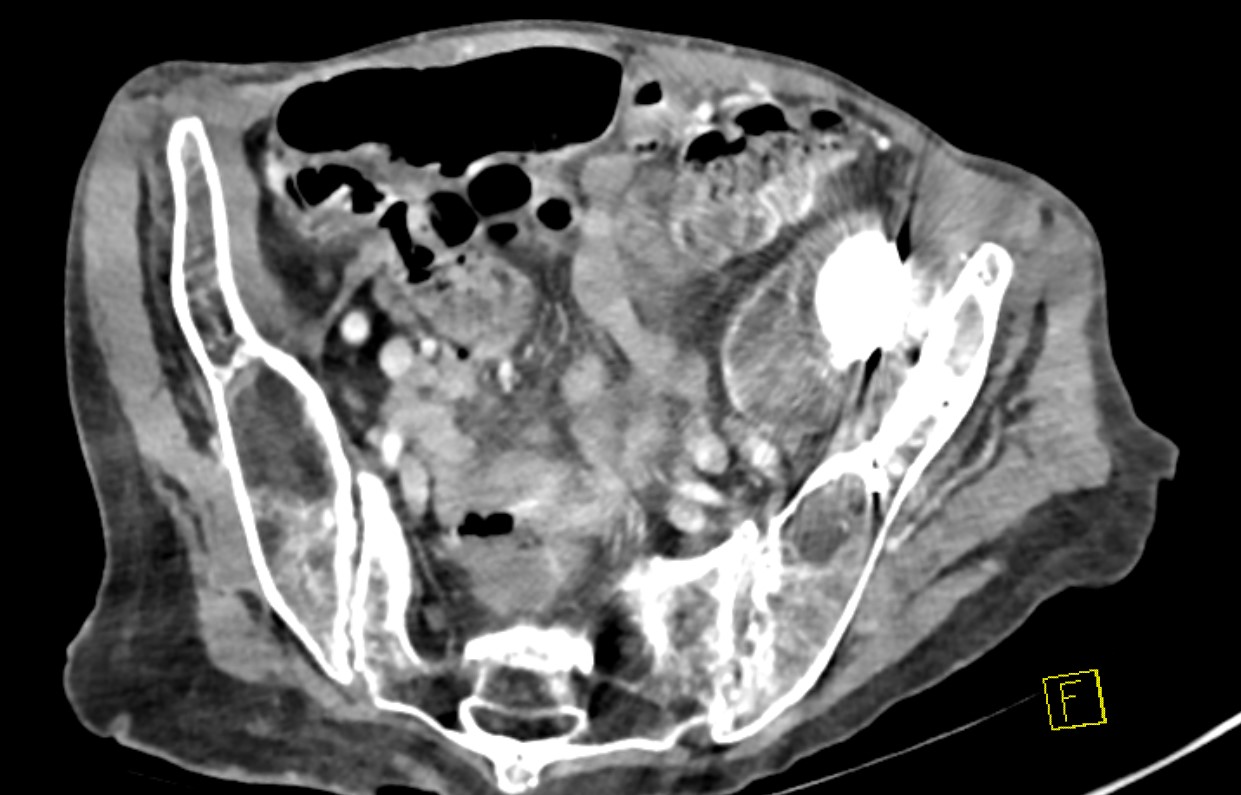

- runs down medial border of psoas

- psoas separates external iliacs & intrapelvic surface of anterior column

Intra-pelvic cement / components

- danger with removal / revision

- CT angiogram pre-operatively

- may require separate intrapelvic exposure

- alert general surgeons / vascular surgeons